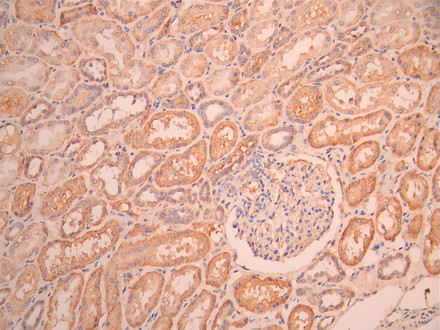

IHC image of CSB-RA002831MA1HU diluted at 1:50 and staining in paraffin-embedded human kidney tissue performed on a Leica BondTM system. After dewaxing and hydration, antigen retrieval was mediated by high pressure in a citrate buffer (pH 6.0). Section was blocked with 10% normal goat serum 30min at RT. Then primary antibody (1% BSA) was incubated at 4°C overnight. The primary is detected by a Anti-Human lgG, Fcy Fragment Specific labeled by HRP and visualized using 0.05% DAB.